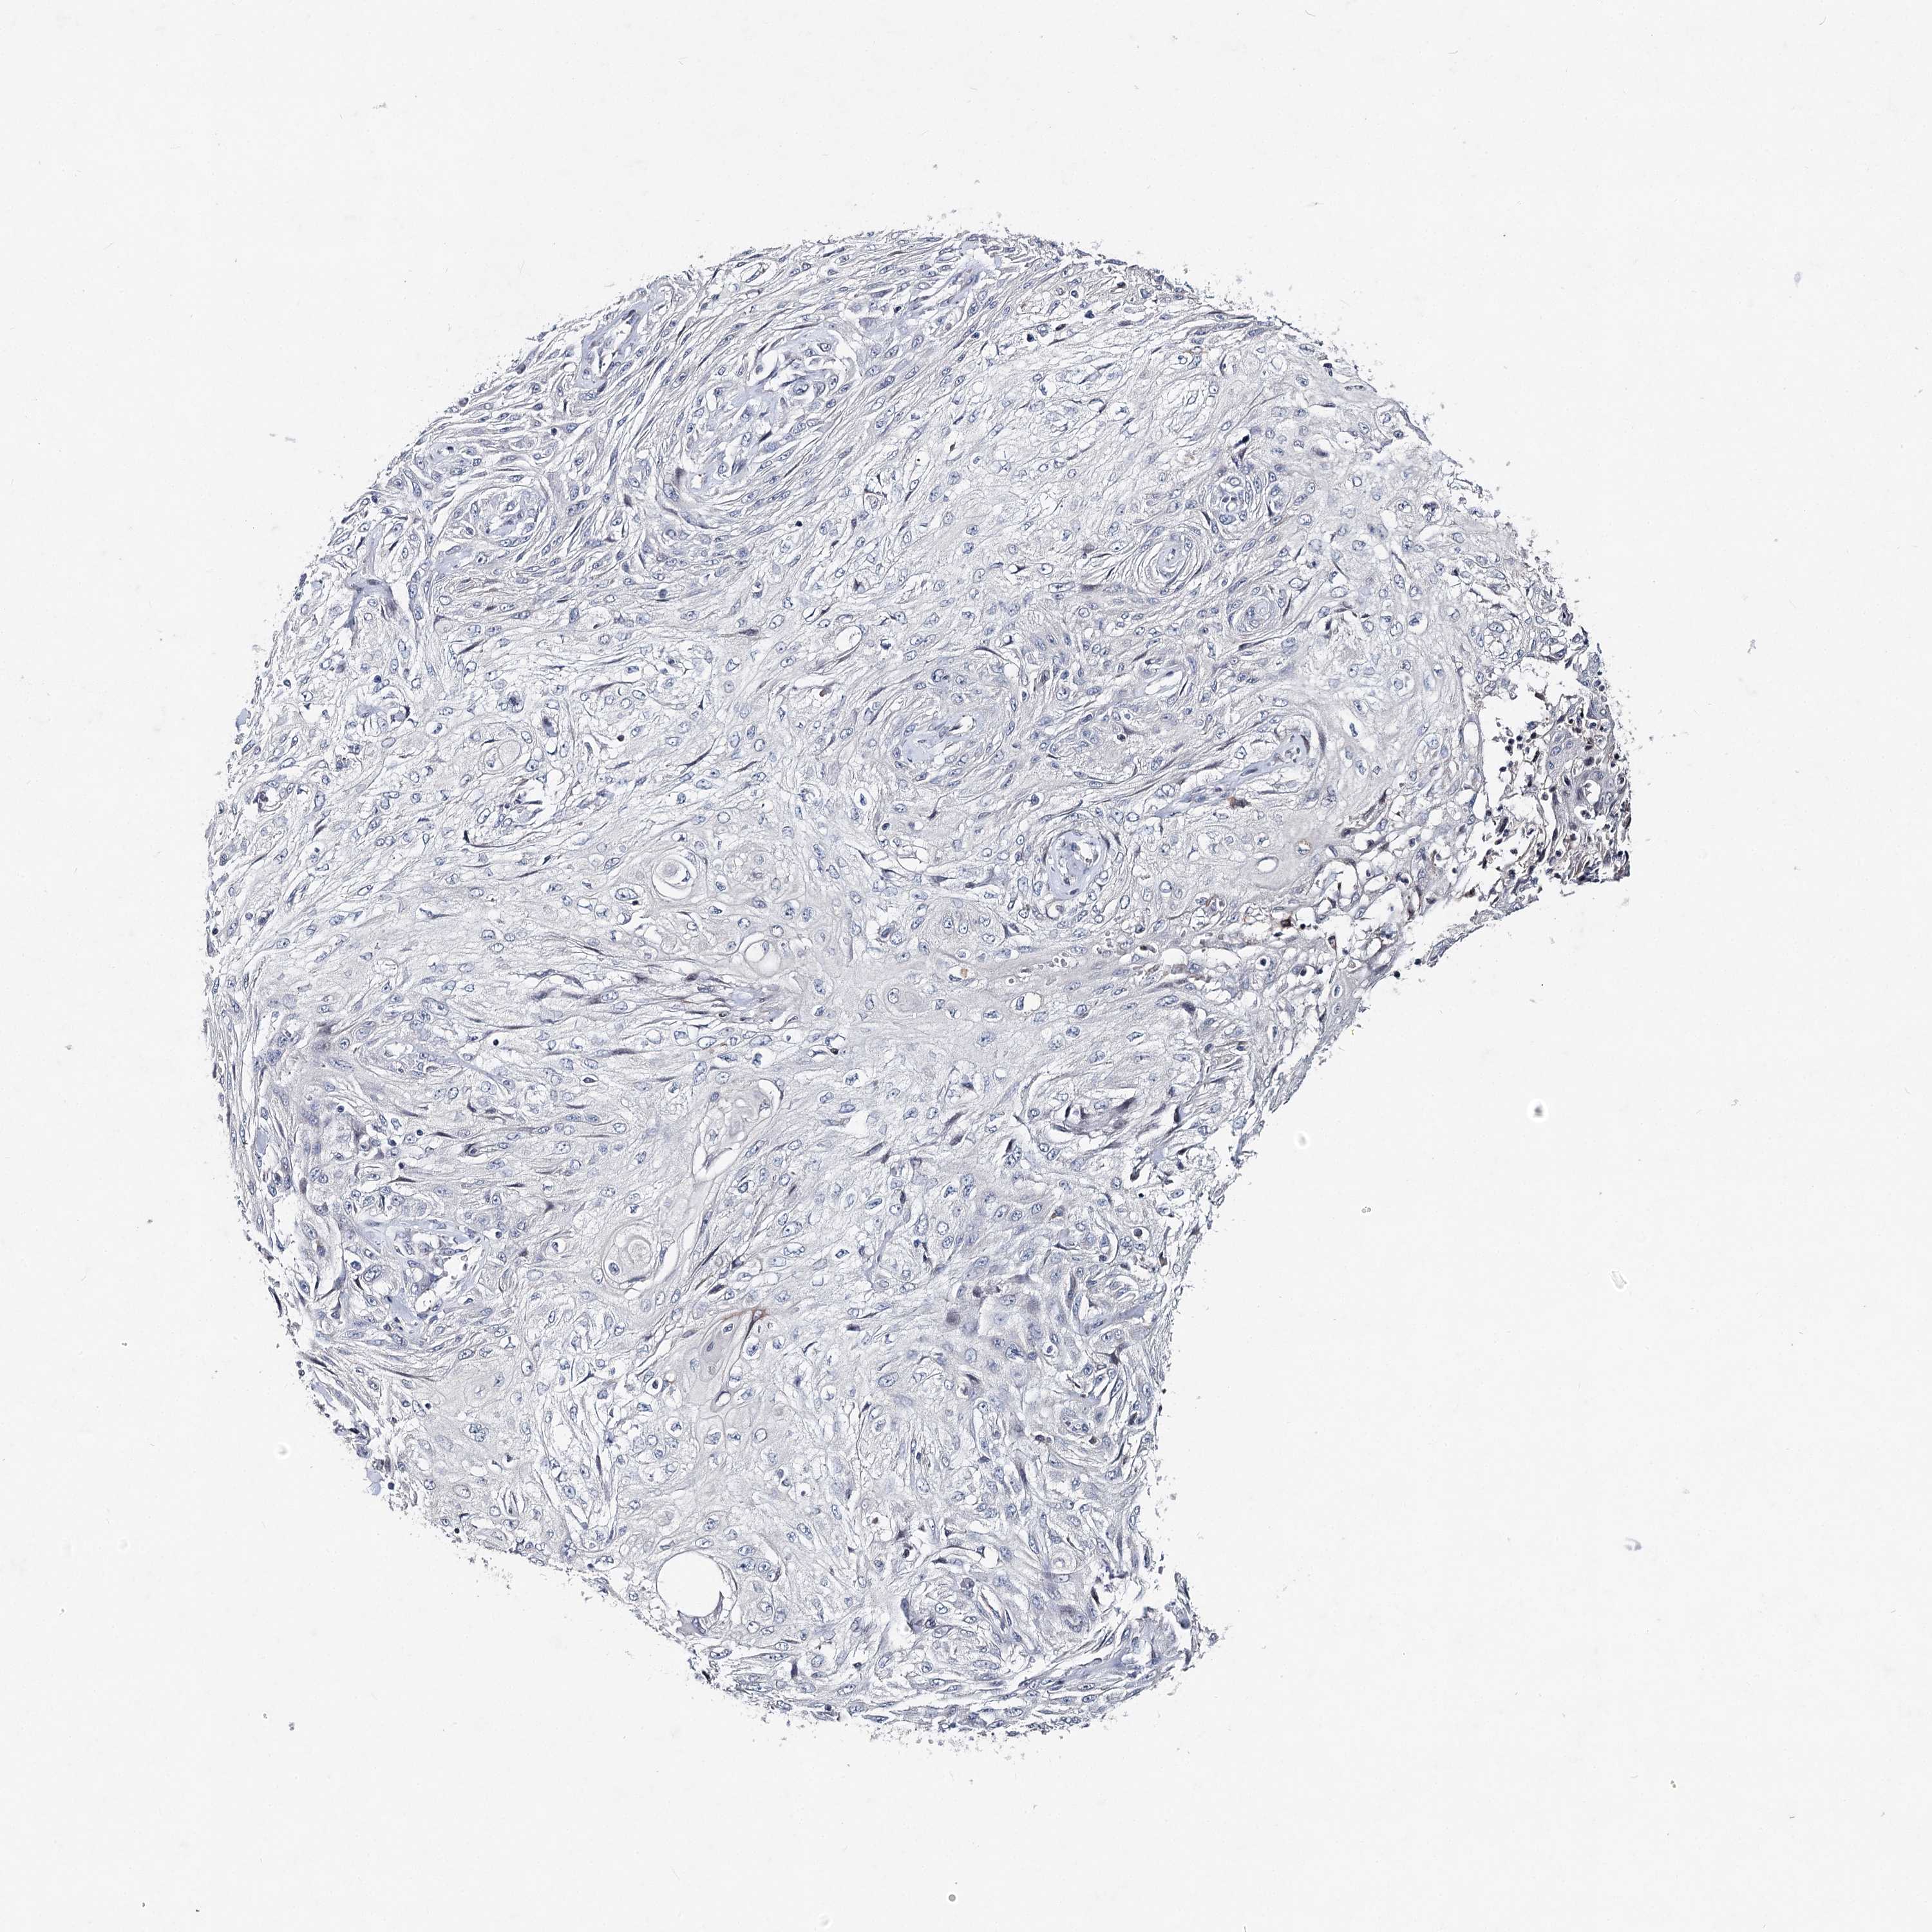

CANCER SKIN CANCER Show tissue menu

Basal cell and squamous cell cancer

SKIN CANCER - Protein expressioni

A mouse-over function shows sample information and annotation data. Click on an image to view it in a full screen mode. Samples can be filtered based on level of antibody staining by selecting one or several of the following categories: high, medium, low and not detected. The assay and annotation is described here.

Each image is clickable and will lead to virtual microscopy that enables deeper exploration of all samples and also displays staining intensity scores, fraction scores and subcellular localization as well as patient and tissue information for each sample.

Antibody HPA038449

Staining

High

Medium

Low

Not detected

Intensity

Strong

Moderate

Weak

Negative

Quantity

>75%

75%-25%

<25%

None

Location

Nuclear

Cytoplasmic/membranous

Cytoplasmic/membranous,nuclear

Squamous cell carcinoma in situ, NOS

Squamous cell carcinoma, NOS

Basal cell carcinoma

Adnexal tumor, benign